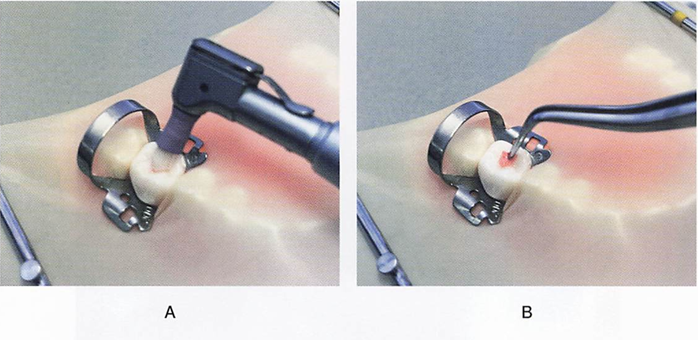

75歳の男性。慢性歯周炎に対する歯周基本治療終了後、3か月間隔で歯周病のメインテナンスと初期の根面う蝕の管理としてフッ化物歯面塗布を行っている。来院時、歯周ポケットの検査を行った後に用いる器材の写真を別に示す。 3番目に用いるのはどれか。1つ選べ。

a. ①

b. ②

c. ③

d. ④

解答を見る

d